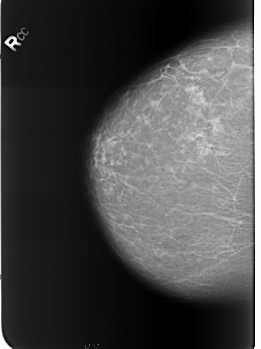

B_3253_1.RIGHT_CC

RIGHT_CC LINES 5576 PIXELS_PER_LINE 4176 BITS_PER_PIXEL 12 RESOLUTION 50 NON_OVERLAY

FILE: B_3253_1.LEFT_CC.OVERLAY

TOTAL_ABNORMALITIES 3

ABNORMALITY 1

LESION_TYPE CALCIFICATION TYPE LUCENT_CENTER DISTRIBUTION N/A

ASSESSMENT 2

SUBTLETY 5

PATHOLOGY BENIGN_WITHOUT_CALLBACK

ABNORMALITY 2

ABNORMALITY 3